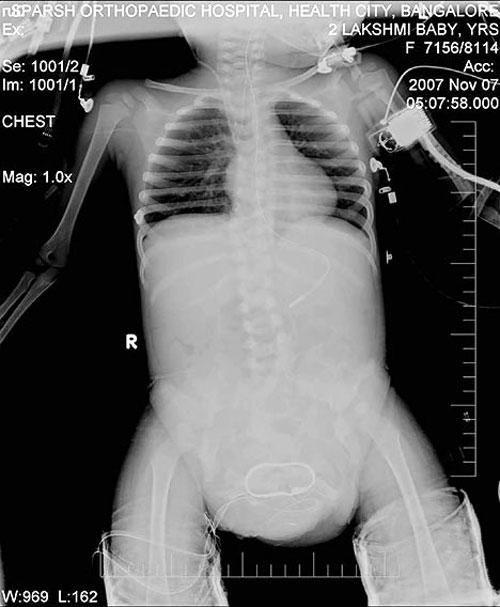

Врачи из Бангалорской клиники «Спарш» согласились провести дорогостоящую операцию по удалению лишних конечностей у девочки бесплатно. В противном случае Лакшми не дожила бы до зрелого возраста.

Сложнейшая операция была благополучно проведена в ноябре 2007 года. Операция длилась 27 часов…